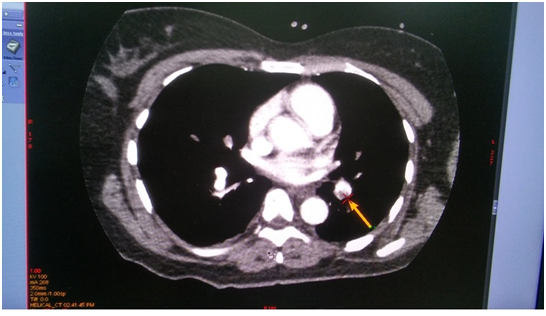

On the next day, at the day time, she felt progressive dyspnea. She was transferred to the intensive care department, where the suggestion of acute lung artery thromboembolic was taken, taken into account the character of dyspnea and extremely low level of blood saturation 60%, with weak response to oxygen therapy. The suggestion was approved by the chest tomography, where the thrombosis of both central lung arteries was revealed (Figure 1-4). After the short discussion among the colleagues, the procedure of thrombolysis was performed. We considered the extremely bad condition of the patient, weak response to oxygen therapy, young age and a kind of the operation. There were no pass to any cavity, no anastomosis, the inserted drainage system, to let blood flow out. Additionally, we had blood cell-save machine “Haemonetics Cell Saver 5+” (USA) to reinfuse blood and decrease blood loss.

Figure 1 (CT of thromboembolism in the left LA).

Figure 2 (CT of thromboembolism in the right LA).

Figure 3 (CT of thromboembolism in the left LA).

Figure 4 (CT of thromboembolism in the right LA).